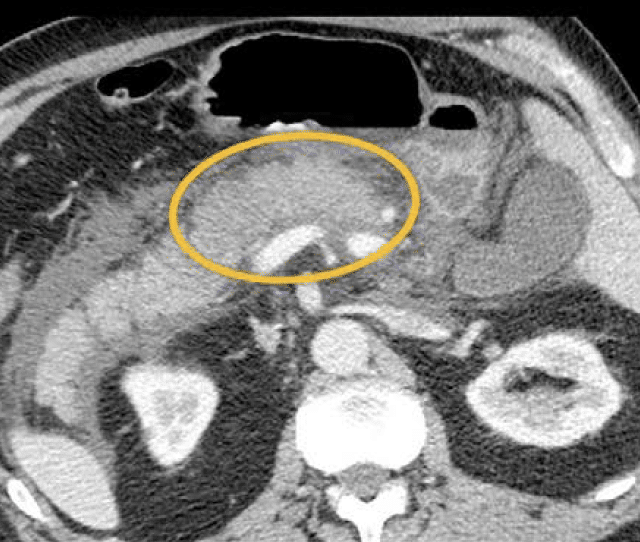

Surenth starter pr. 1. september 2023 i PhD stilling omhandlende pancreasforskning. og så skal der stå en sætning mere her, før at layoutet passer.